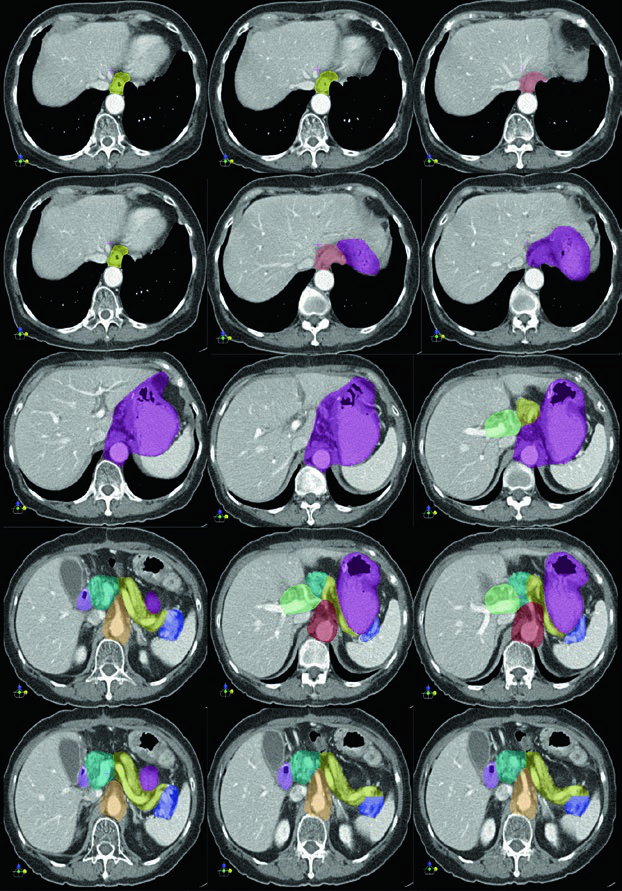

Caso 1: T1N1M0 Adenocarcinoma da Cárdia — Gastrectomia Total

Neste caso, o CTV engloba a anastomose esofagojejunal, o ligamento hepatogástrico, a artéria celíaca e o hilo esplênico. Como se trata de gastrectomia total em tumor da cárdia com linfonodo positivo, não há remanescente gástrico a incluir, mas os volumes nodais devem ser amplos.

Caso 2: T3N3M0 Adenocarcinoma do Corpo — Gastrectomia Distal

Com doença T3N3, o CTV é extenso: inclui anastomose gastrojejunal, estômago remanescente, artéria celíaca, hilo esplênico e leito tumoral pancreático. Esse cenário exige atenção especial às restrições de dose nos órgãos de risco — particularmente rins e fígado — pois o volume de tratamento é considerável.

Caso 3: T2N1M0 Adenocarcinoma de Antro/Piloro — Gastrectomia Distal

No adenocarcinoma de antro/piloro, o CTV abrange a anastomose gastrojejunal, o estômago remanescente, o ligamento hepatogástrico e o coto duodenal. A cobertura do hilo esplênico é opcional neste cenário. A inclusão do coto duodenal é preferencial em gastrectomias parciais por tumores distais/antrais, mas não deve ser incluída em pacientes com tumores proximais submetidos a gastrectomia total.